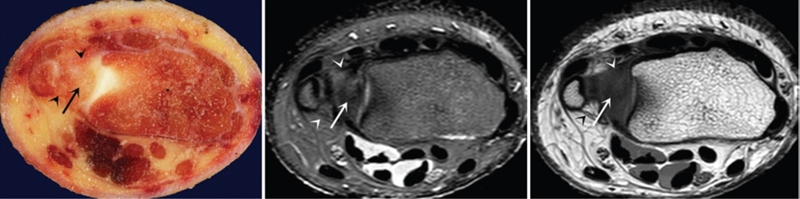

ⅡA,TFC局部变薄,但结构完整

ⅡB,TFC局部变薄,但结构完整,月骨软骨厚薄不均

ⅡC,TFC中心撕裂,月骨软化,月三角韧带完整

ⅡD,TFC中心撕裂,月骨软化,月三角韧带缺如

图30 ⅡE,TFC中心撕裂,月骨、尺骨软骨软化,月三角韧带缺如,桡尺关节骨质增生